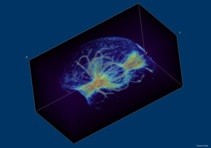

La Resonancia Magnética de Imagen (RMI o IRM en inglés), también conocida como Tomografía por Resonancia Magnética (TRM) o Resonancia Magnética Nuclear de Imagen nuclear (RMNI o NMRI en inglés) es una técnica no invasiva que utiliza el fenómeno de la resonancia magnética para obtener información sobre la estructura y composición del cuerpo a analizar. La información es después procesada transformada en imágenes.